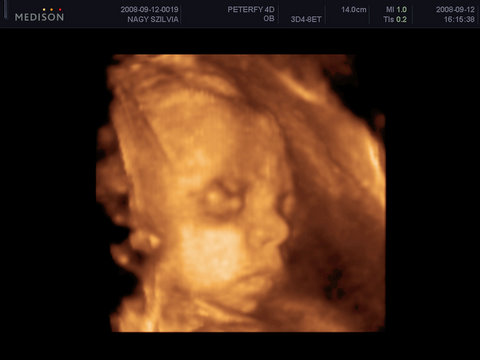

Szombaton a genesisben megneztek ot es Lalikankal minden rendben :D

Ja! A legújabb fotó a Művésznőről!